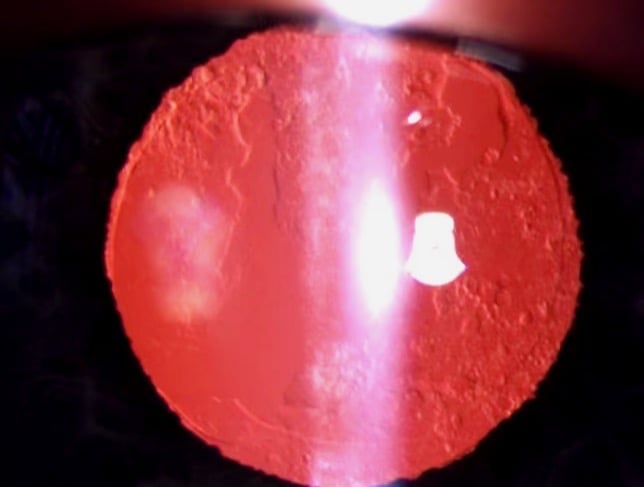

Durch das Wachstum von verbliebenen Linsenzellen im Bereich des peripheren Linsenkapselsackes kann es im Laufe von 1 - 5 Jahren zur Ausbildung von Nachstar kommen, d.h. Auflagerungen auf der Linsenkapsel, die wenn sie im optischen Zentrum liegen, das Sehvermögen erheblich reduzieren können.

Man unterscheidet eine fibrotische und eine regeneratorische Form, letztere geht auch häufig mit einer stark erhöhten Blendungsempfindlichkeit einher.